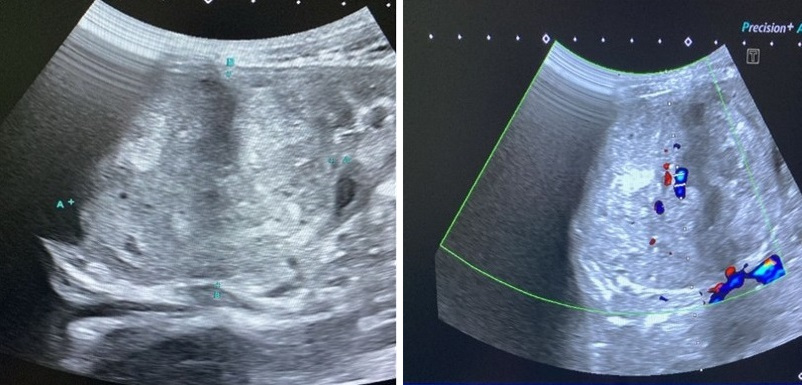

Se solicita ecografía abdominal, donde se aprecia una gran masa renal bien definida, heterogénea, afectando a tercio superior-medio de riñón izquierdo, que alcanza los 8,2 x 6,7 x 6 cm, que presenta flujo en su interior el estudio doppler, hallazgos sugestivos de proceso orgánico tumoral, probablemente tumoración de Wilms, objetivándose ligera ectasia pielocalicial asociada.

La paciente es trasladada al centro de Oncopediatría de referencia, donde recibe tratamiento según protocolo UMBRELLA PROTOCOL SIOP 2016, con el diagnóstico de tumor de Wilms estadio I, tipo anaplasia difusa (riesgo alto). Tras quimioterapia y cirugía, en este momento se encuentra libre de enfermedad (Figura 1).

Figura 1. Pruebas de imagen